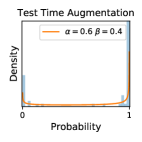

To model how different classifiers will respond to a given input , we assume that the prediction from classifier is sampled from a beta distribution that is characterized by two parameters by and . We further assume that is fixed to the same constant value for all ’s. Under this assumption, each input can be described by ( can be calculated since is fixed), easing further analysis. The Severity Level (SL) of the case represented by image can be characterized by the parameter . The larger the value of , the more severe the case of is. When and are close, the case is ambiguous as the distribution shifts towards being symmetric (i.e. signifying much disagreement among classifiers) rather than being one-sided (i.e. consensus among classifiers that is negative or positive). We provide a set of examples in Figure 2 and also Figure S.8 in the supplementary materials showing how the beta distribution can be used to capture diverse predictions given by an ensemble learner.

5.1 Distribution of Uncertainty Scores

Distribution of Uncertainty Scores Across Different Severity Levels As explained in Section 3, each uncertainty metric essentially defines an order/ranking among the data points. We conducted an analysis to better understand what data will be assigned high uncertainty under a particular uncertainty metric . Picking out the highest ranked data points (), we calculated the ratio of data points from each SL. Figure 4 summarizes the results as box plots for the Kaggle-DR and the Messidor-2 datasets; additional detailed statistics can be found in Table S.1 in the supplementary materials. From the plot and table, SL1 & SL2 examples account for a higher proportion among the top-ranked uncertain examples across the three ensemble methods. This finding matches our intuition that incipient disease examples (SL1 & SL2) are more likely to be considered uncertain by ensemble methods due to their ambiguity.

Comparing the three ensemble methods in Figure 4, the stacking ensemble method has the highest ratios of SL1 & SL2 data among the high-uncertainty examples it identified under both mean and var. TTA showed slightly better performance than MC-dropout but still falls behind the stacking ensemble method. Considering the fact that SL0 examples accounted for the majority of the dataset, the stacking ensemble method was much more precise (specific) in selecting truly ambiguous data points that were difficult to classify. From Figure 3, we can also see that the stacking ensemble method greatly outperformed the other two methods in finding false negatives under both mean and var uncertainty metrics.

In contrast, the MC-dropout method showed the worst overall performance among the three, as it can be seen from the high ratios of SL0 examples among the uncertain negatives in Figure 4. The histograms in Figure 2 provides another perspective to look into the phenomenon, where a decent proportion of MC-dropout model’s predictions on SL0 inputs entailed low confidence (far from 0 or 1), which from another angle explained why MC-dropout was less specific in terms of lower FNP; many no-DR inputs (i.e. SL0) were erroneously assigned high uncertainty by MC-dropout models.

It is still an open question why the evaluated MC-dropout networks signaled relatively high uncertainty on SL0 & SL3 & SL4 data that are less likely to be ambiguous. We conjecture that much of the “uncertainty” indicated by disagreement among test-time dropout samples actually reflects the stochastic nature of dropout networks rather than the real decision uncertainty associated with the data. It is worth noting that the MC-dropout model we evaluated was not weak per se; they all achieved above Area Under Curve (AUC) scores on test sets. The weakness of individual test-time samples (which explains their low-confidence predictions on SL0 & SL3 & SL4) might have been hidden when they are aggregated into an ensemble—a well-known advantage of ensemble learning. Our results suggested that the uncertainty information given by implicit ensemble methods such as MC-dropout and TTA might not be as reliable as that from explicit ensemble approaches (e.g., stacking ensembles). Similar findings on MC-dropout can be found in some previous papers [1].